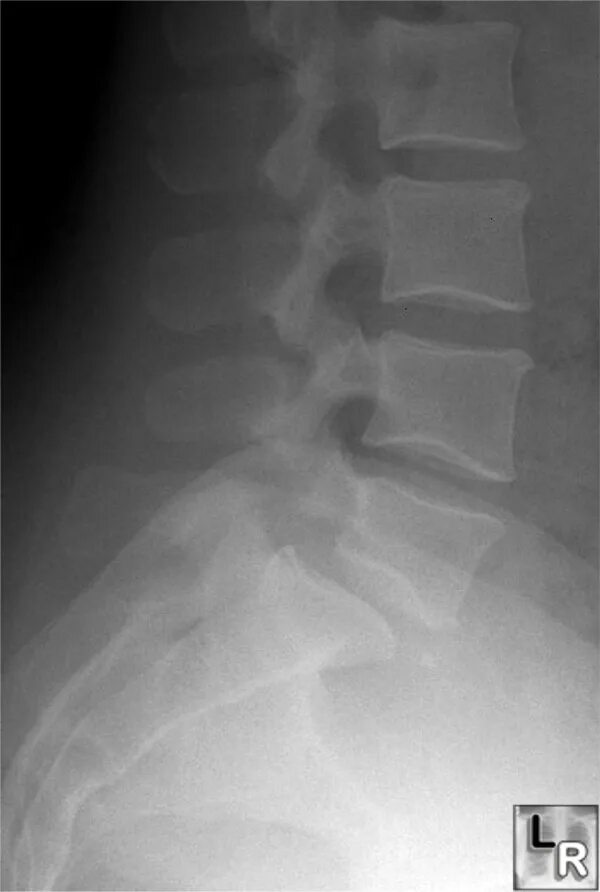

Смещение 5